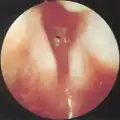

Subglottic stenosis is graded according to the Cotton-Myer classification system from one to four based on the severity of the blockage. Grade 1 is up to 50% obstruction, Grade 2 is 50-70% obstruction, Grade 3 is 70-99% obstruction, and Grade 4 is with no visible lumen.[5]

Grade 1 subglottic stenosis -

Grade 2 subglottic stenosis -

Grade 3 subglottic stenosis -

Grade 4 subglottic stenosis